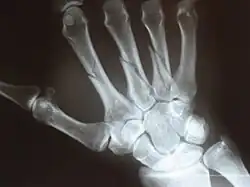

Fracture

The neck of a metacarpal is a common location for a boxer's fracture, but all parts of the metacarpal bone (including head, body and base) are susceptible to fracture. During their lifetime, 2.5% of individuals will experience at least one metacarpal fracture. Bennett's fracture (base of the thumb) is the most common.[4] Several types of treatment exist ranging from non-operative techniques, with or without immobilization, to operative techniques using closed or open reduction and internal fixation (ORIF). Generally, most fractures showing little or no displacement can be treated successfully without surgery.[5] Intraarticular fracture-dislocations of the metacarpal head or base may require surgical fixation, as fragment displacement affecting the joint surface is rarely tolerated well.[5]

Multiple fractures of the metacarpals (aka broken hand). (Right hand shown with thumb on left.) -